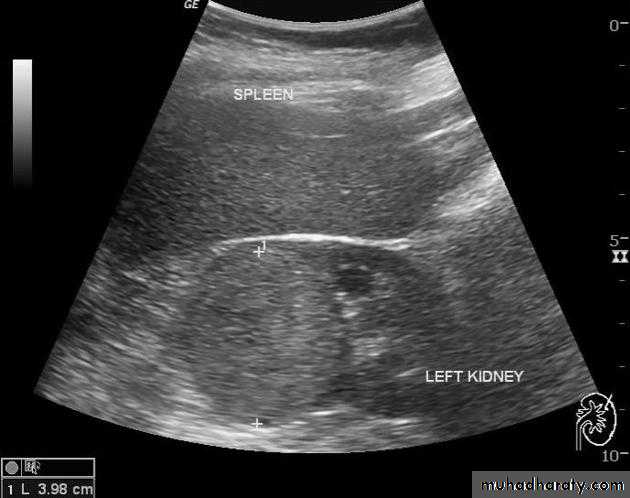

Renal cysts

‘renal pseudotumour’ or column of Bertin

Multiple renal masses include:

• Multiple simple cysts• Polycystic disease